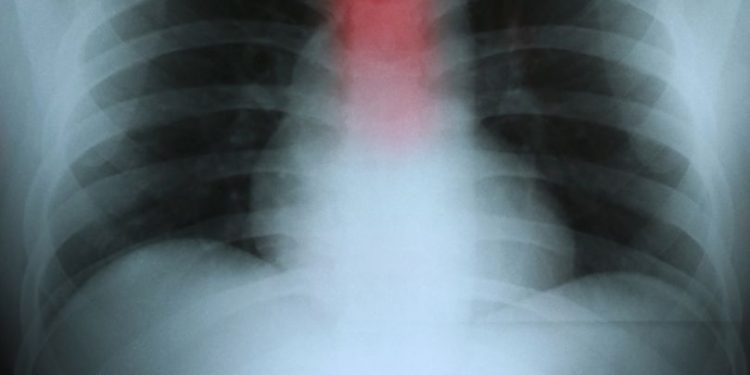

If the tumor continues to grow, it may block the esophagus and cause symptoms such as difficulty swallowing, vomiting, and chest pain that occurs a few seconds after eating or drinking. The cancer also can lead to weight loss and dry mouth.

There are two main types of esophageal cancer: squamous cell carcinoma and adenocarcinoma. Squamous cell carcinoma begins in the flat cells that line the esophagus, and it can occur anywhere along the esophagus. Adenocarcinoma, which grows from glandular cells that line the esophagus, usually develops in the lower part of the esophagus near the stomach.